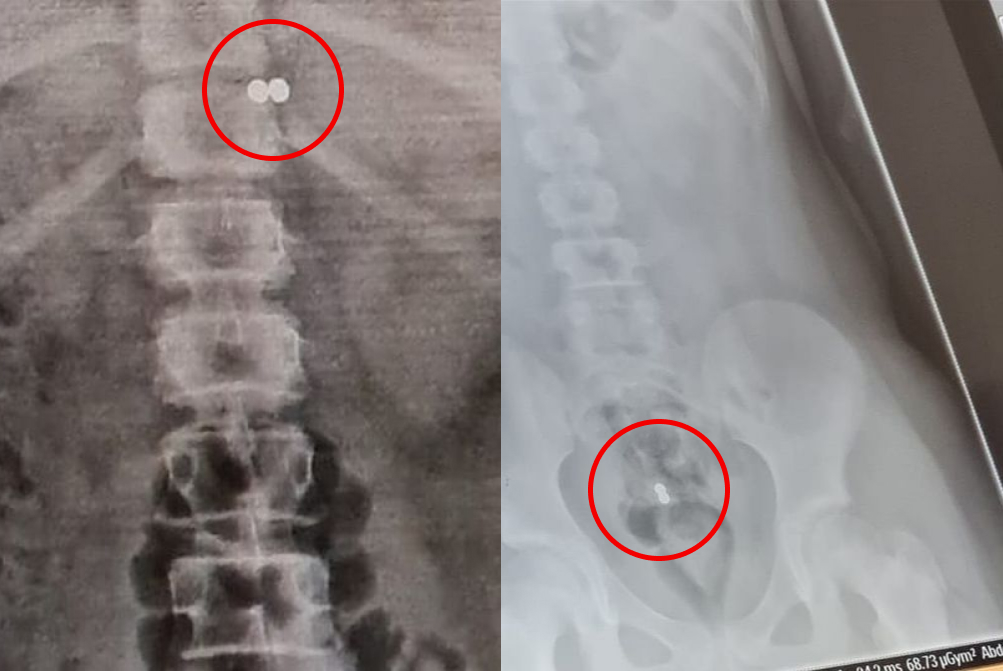

Магнитные шарики на рентгене: Интересные находки

Раздел: Картинки на заметку